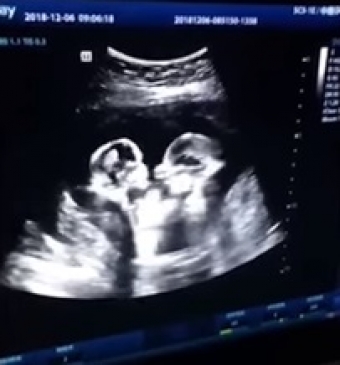

China: తల్లి గర్భంలోనే కవలల ఫైటింగ్... వీడియో విడుదల... బాక్సర్లవుతారంటున్న నెటిజన్లు!

• అల్ట్రాసౌండ్ స్కానింగ్ ను వీడియో తీసిన భర్త

తోడబుట్టిన వారు కొట్లాడుకుంటారన్న సంగతి అందరికీ తెలుసు. అదే వారు కవలలైతే పోటీ ఇంకాస్త ఎక్కువగానే ఉంటుంది. కానీ, తల్లి గర్భంలో ఉన్న సమయంలోనే ఇద్దరు కొట్టుకుంటుంటే... ఆ వీడియో ఇప్పుడు తెగ వైరల్ అవుతోంది. చైనాకు చెందిన ఓ మహిళ గర్భంతో ఉన్న వేళ, వైద్యులు ఆమెకు అల్ట్రాసౌండ్ స్కానింగ్ తీసిన వీడియో ఇది. ఆమె గర్భంలోని కవలలు ఒకరితో ఒకరు ఫైటింగ్ కు దిగారు. దీన్ని వీడియో తీసిన బిడ్డల తండ్రి సోషల్ మీడియాలో పోస్ట్ చేయగా, వీరిద్దరూ బాక్సర్లు అయిపోవడం ఖాయమంటూ నెటిజన్లు ప్రశంసిస్తున్నారు. బయటకు వచ్చాక ఇంకెలా తన్నుకుంటారోనన్న సందేహాలను వ్యక్తం చేస్తున్నారు. తెగ వైరల్ అవుతున్న వీడియోను చూసేయండి.